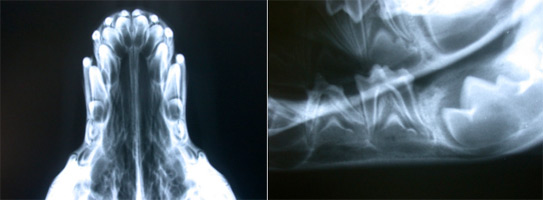

Riscontriamo inoltre sovente anomalie di occlusione, dobbiamo

distinguere quelle scheletriche, dove si ha un allungamento o un

accorciamento di mandibola o mascella, da quelle dento-alveolari in cui

si ha il mal posizionamento di uno o più denti. Una diagnosi precisa può

essere confermata radiologicamente in proiezione latero-laterale:

infatti nella normocclusione il punto apicale

della mandibola si trova sulla stessa linea del punto apicale della

mascella, inoltre le cuspidi degli incisivi inferiori occludono con la

superficie palatina degli incisivi superiori (dentatura a forbice), e il

canino inferiore è sito fra il terzo incisivo e il canino superiore. Nel

prognatismo l’apice della mandibola è sito anteriormente all’apice della

mascella, e in alcuni casi (boxer, pechinesi..) è caratteristica di

razza.

Nell’enognatismo, sempre grave difetto,  l’apice della mandibola è sito

posteriormente  all’apice della mascella.  |